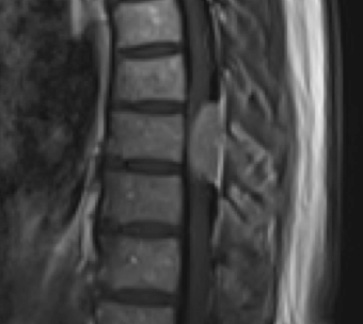

Postoperative MRI T1w demonstrating a gross total resection

Postoperative MRI T1w demonstrating interval resection with cord re-expansion (blue arrow)